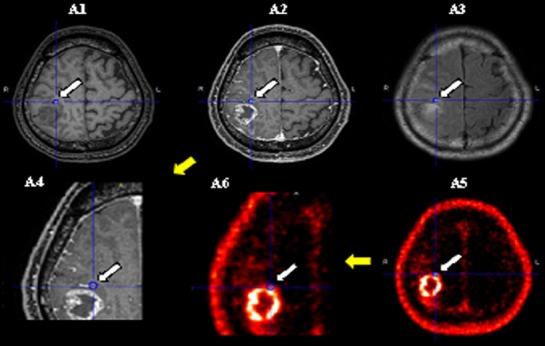

Anti-[F]FACBC was administered to 40 patients with clinically suspected high- or low-grade gliomas, followed by PET imaging. T1-weighted, contrast-enhanced T1-weighted, and fluid-attenuated inversion recovery (or T2-weighted) magnetic resonance imaging (MRI) scans were obtained to plan for the tissue collection. Tissues were collected from either "areas visualized using anti-[F]FACBC PET imaging but not using contrast-enhanced T1-weighted imaging" or "areas visualized using both anti-[F]FACBC-PET imaging and contrast-enhanced T1-weighted imaging" and were histopathologically examined to assess the diagnostic accuracy of anti-[F]FACBC-PET for gliomas.

对40例临床疑似高级别或低级别胶质瘤患者给予抗-[F]FACBC,随后进行PET成像。获取T1加权、对比增强T1加权和液体衰减反转恢复(或T2加权)磁共振成像(MRI)扫描以计划组织采集。组织取自“使用抗-[F]FACBC PET成像可见但使用对比增强T1加权成像不可见的区域”或“使用抗-[F]FACBC-PET成像和对比增强T1加权成像均可见的区域”,并进行组织病理学检查以评估抗-[F]FACBC-PET对胶质瘤的诊断准确性。